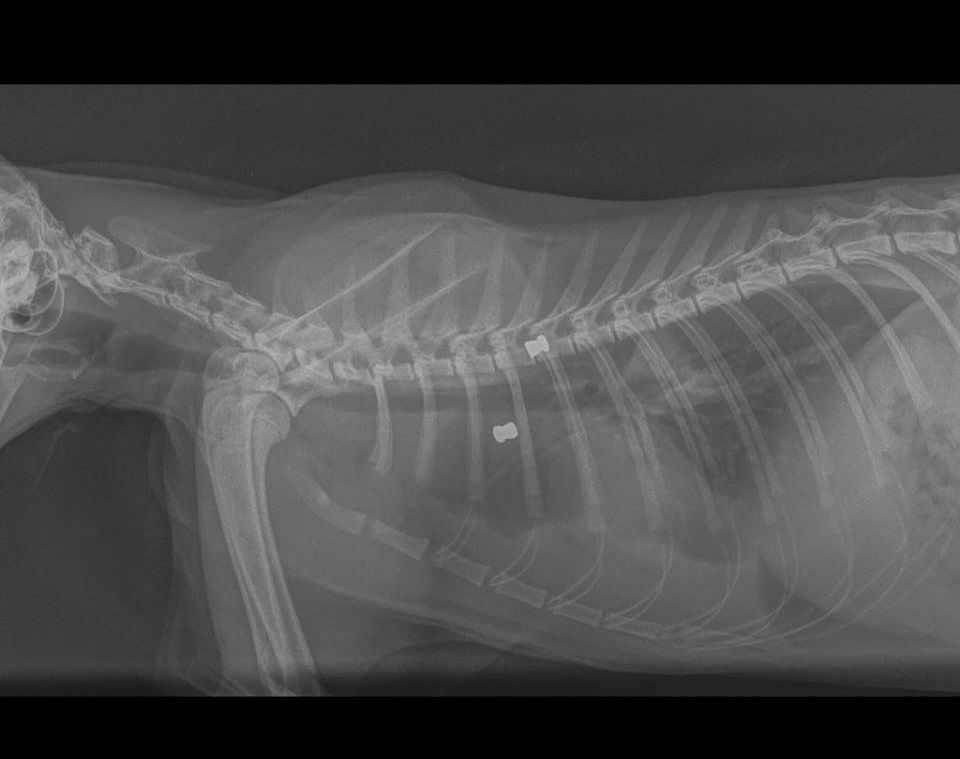

Η γυναίκα μετέφερε το τραυματισμένο ζώο στο κτηνιατρείο στις 27 Μαρτίου και η ακτινογραφία, όπως επισημαίνει ο κτηνίατρος Αντώνης Λιονάκης - που έφερε και στη δημοσιότητα την υπόθεση και μίλησε στο www.zoosos.gr - έδειξε τα δύο σφαιρίδια στο κορμί της γάτας αλλά το υγρό που είχε συγκεντρωθεί στον θώρακα από την μόλυνση. Μάλιστα σύμφωνα με τον κτηνίατρο το ζώο πρέπει να είχε πυροβοληθεί περίπου τέσσερις μέρες πριν μεταφερθεί για περίθαλψη.

Η ακτινογραφία έδειξε τα δύο σφαιρίδια...

Η ακτινογραφία έδειξε τα δύο σφαιρίδια...

Το ένα από τα σφαιρίδια αφαιρέθηκε επιτυχώς και λίγες μέρες αργότερα υποχώρησε και η μόλυνση και το ζώο σταδιακά ανάρρωσε. Εντούτοις ο άνθρωπος που βασάνισε έτσι το ζώο παραμένει άγνωστος και φυσικά είναι πολύ πιθανό να το κάνει ξανά και ξανά.

Το ένα αφαιρέθηκε χειρουργικά.

Το ένα αφαιρέθηκε χειρουργικά.

Μας προσκομίστηκε η γατούλα αυτή, με τραύματα από σκάγια αεροβόλου όπλου, αιμορραγία και μόλυνση στο θώρακα (πυοθώρακα), σε πολύ βαριά κατάσταση. Ένα από τα σκάγια αφαιρέθηκε χειρουργικά. Ευτυχώς μετά από αρκετές ημέρες νοσηλείας ανέρρωσε πλήρως.